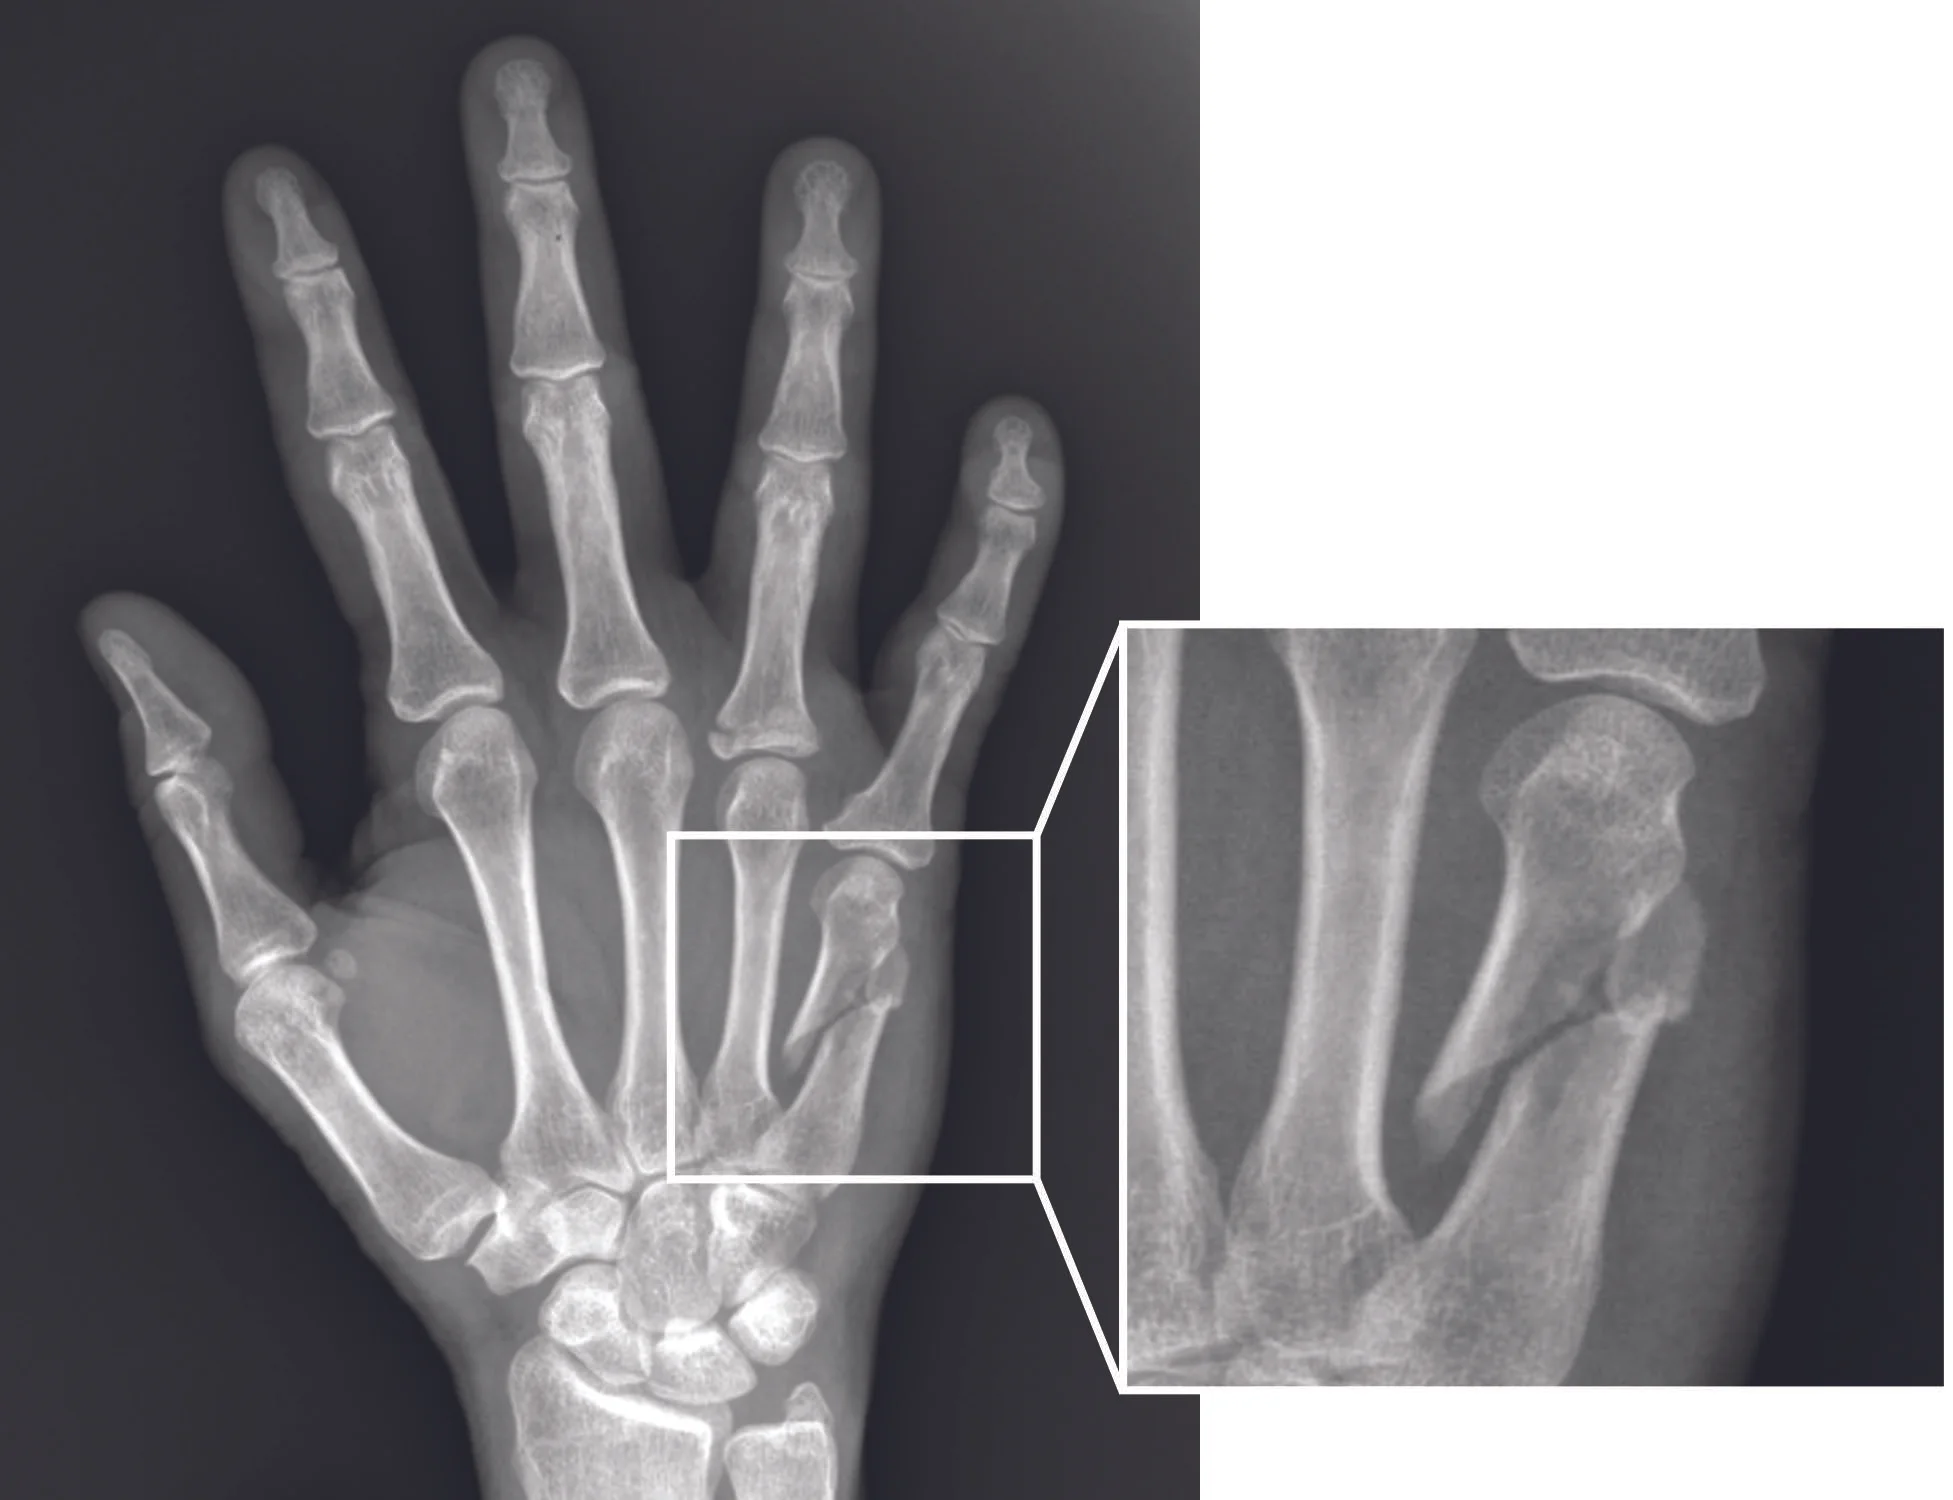

Cureus | Management of Fifth Metacarpal Neck Fracture (Boxer's Fracture): A Literature Review"Don't ever doubt that a small group of considered and committed citizens can change the world. Indeed, it is the only thing it has. " Margaret Mead "Never doubt that a small group of considered and committed citizens can change the world. In fact, it's the only thing he has. "Cureus is on a mission to change the long-standing paradigm of the medical publication, where the presentation of the research can be costly, complex and consumed for a long time. RATED BY 4 READERS 7.7 7.6 8.0 7.0 , , , Quinto Metacarpal Management Neck Fracture (Buxer Fracture): A literature review , , , , Published: 28 July 2020 - Yeah? 10.7759/cureus.9442 Cite this article as: Hussain M, Ghaffar A, Choudry Q, et al. (28 July 2020) Management of the fifth metacarpal neck fracture (Bober fracture): a literature review. Cureus 12(7): e9442. doi:10.7759/cureus.9442 AbstractBoxer's fracture is the fifth metacarpal neck fracture resulting from direct trauma to the clenched fist. Worldwide, this type of fracture is the most typical presentation to emergency departments. The management of the fifth metacarpal fractures varies from one environment to another. Conservative management is the preferred option for closed fractures, non-acmonulated, non-acmalred, while open fractures, significant angulation, rotational deformity and intra-articular extension are recognized indications for surgical intervention. The scope of this article covers the results of a bibliographic review that examines the management strategies of such fractures. Introduction " Background 33% of patients with manual fractures are metacarpal fractures. Most metacarpal fractures involve the fifth metacarpal. A subcapital/neck of the fifth metacarpian fracture is commonly known as a boxer fracture. It is more common in men than in women, and peaks of incidence to the age group of 10 to 29 years. These fractures can usually be managed conservatively, however, several factors such as longitudinal shortening, angulation, malpractice, bone loss, and soft tissue injury are indications for surgical fixation. This literary review aims to discuss all possible management options for the fifth metacarpal bone fractures. RevisionPatoanatomy and Diagnosis The fracture of a boxer is typically a result of direct trauma to a tight fist where the energy is transferred through the fifth metacarpia axially and most of it results in the apex's dorsal angulation due to the pull of the interosseous muscles of the hand. Like any other long bone fractures, metacarpal bone fractures also follow the same pattern of descriptive classification, i.e. open or closed, intraarticular or extraarticular, oblique, spiral, transverse or minute comminution. The neurovascular package runs adjacent to a metacarpal and may be damaged in displaced fractures, which requires surgical intervention. When examining a possible fifth metacarpian fracture, a doctor should pay special attention to checking any skin rupture (fighting effects), neurovascular state, pseudo claw or rotational alignment, and the hand not wound should be compared. Early minutia debris and antibiotics are required for patients with combat bites, as amputation may be necessary in certain cases with chronic bone vain and tendon infection. Flat x-rays (former, lateral and oblique) are the gold standard for diagnosis and for determining angulation (Figure -). Angulation should be measured at more than 15 degrees, as normal angulation of the fifth metacarpal neck is 15 degrees. KocaoÄŸlu S and colleagues recently suggested the use of ultrasonography to detect metacarpal fractures in the emergency department. Hidden metacarpal fractures require an early computed tomography (CT) for rapid diagnosis .PA = PosteroanteriorNo-operatory management A non-complicated fracture - closed, not annulled, and non-evilated or otherwise displaced - fifth metacarpian fracture can be handled with initial immobilization with a ulnar rubber spine. Alternatively, a more minimalist approach to lure the small toe and swirl together, also known as a friend tap, can be used in non-complicated cases. The conventional teachings suggest that the position of the hand for the fractured spine should be: the wrist extended to 20 degrees, 60-70 degree of bending in the metacarpofalangeal (MCP), and the interfalangeal joints in extension. The risk of rotational deformity is significantly reduced by strangulation/taping of a friend. Complete immobilization with a rubber of ulnar or shortcut of friend, which provides immediate motion have relatively comparable functional results. However, a study conducted by Bansal R reported a greater degree of patient satisfaction, less follow-up, and a return before work when dealing with the partner disappearing comparatively to spread. Many authors recommend accepting angulation up to 70 degrees in small fractures of the finger metacarpy neck. In spite of these recommendations, a biomechanical study conducted in 1999 concluded a loss of 8% in the grip force bendor digiti minimi and a reduction of 22% in the range of movement associated with 30 degrees of angulation, therefore, suggests a higher limit for acceptable angulation of 30 degrees. The fracture of the boxer with a significant fracture requires a closed reduction. The closed reduction of the angulated fractures can be attempted in an accident and emergency department (A & E); the bending of 90 degrees is reached in the metacarpofalangeal and interfalangeal joints of the fingers. The pressure then applies to the dorsal aspect of the fracture to push the head dorsally flattening the axis. Although this technique is successful in reducing fractures, the maintenance of reduction remains a bending problem. Harris and colleagues presented a document describing the longitudinal traction of the fifth metacarpal with subsequent immobilization with a plaster. The results indicated more than 80% of the initial correction of the angulation with only 1 degree of correction loss after the plaster interruption in three to four weeks. Operational Management There is a considerable amount of variability in the preferred method for the management of surgical fractures of the fifth metacarpian fracture also known as the fracture of the boxer. We review the literature available in an attempt to summarize the methods used in the current practice to achieve consensus. Two previous studies, including meta-analysis, showed comparable levels of subjective satisfaction with conservative and surgical management. However, objectively, the operating groups showed lower levels of residual dorsal ingulation, although, with longer periods of rehabilitation and off-work time in relation to the conservatively managed group of patients. Both conservative and operating groups exhibited some degree of bad rotational alignment. However, neither of the two methods led to a significant loss in the range of movement or grip force. With the above considered, surgical management should only be preferred when there is a strong indication for it. The following are some of the indications for the surgical management mentioned in the literature. Open fractures: Irrigation and debridation of the wound, together with open reduction and internal fixation;2: Composite fracture or multiple fractures involving multiple metacarpals and/or phalanges;3: Intra-articular fruits particularly when a fragment avoids smooth movement of the joint;4: Fractures that extend to the head of the metacarpal with displacement Ø1 mm;5: Displacement. This is a quite unique criterion in terms of its relevance to which metacarpal involvement is involved. Flying angulation can result in a reduction in the grip force, pseudo claw and a visible deformity of the metacarpia head in the palmar aspect. In addition, ulnar metacarpals have greater compensatory metacarpal joint flexibility and therefore can tolerate a higher degree of fly angulation when compared to radial metacarpals. The acceptable flies of the distal fragment are 10, 20, 30 and 40 for the metacarpals second, third, fourth and fifth respectively;6: Shortening of ± 5 mm;7: Malunion or non-union;8: Inability to reduce a fracture with conservative methods; and9: Rotational deformity. Fixing technique Different surgical techniques are currently used for the surgical management of the boxer fracture. The final decision on which it should be used depends on the surgeon's preference by taking into account both the pros and cons of each technique and the patoanatomy of the individual case. Kirschner Wires (K-Wires)Most of the simple fractures of the closed metacarpal neck can be managed conservatively by flexing the digit in the metacarpopharphalangic and proximal joints and applying a dorsal force directed along the plane of the first phalanx. Stable fractures can be spurred externally. However, if the fracture is considered to be unstable, more stabilization can be used when pricking with K wires. K wires are minimally invasive and easy to use as an implant for the stabilization of percutaneous and open fractures. However, there are certain cons with the use of K-wires as possible neurovascular injury, tendon adhesions, pin site infection, and defy the pin. Available in different diameters, the K wires are driven using a drill in the bone in the ulnoadial direction, radiulnar or through the center of the bone. The K-wire must pass the fracture site ideally at an angle of more than 45 degrees. K wires are inserted using four techniques (cross-the-scene, pinning crucifix, pinning of bouquets and a single K-wire in Lazy S fashion), which are described below. Crossing: Two wires are inserted bicortically in a retrograde form from a distal entry point to the fracture site. The pins are avoided crossing the fracture site to avoid rotation changes in the fragment. A diameter K ring of 0.9 or 1.1 mm is used. Pinning crucifix: A 1.6 mm thicker diameter wire is advanced through the head of the metacarpal retrogradely on the spinal canal. The second thinner wire is driven from the radial aspect in the heads of the fractured metacarpath and an adjacent metacarpal, forming a crucifix form. Bouquet pinning: Multiple, typically three, K wires are anchored centrally through the intramedular cavity. The form resulting from the wires resembles a bouquet, since the distal ends are usually given a dorsal curve to support the reduction. A single K-wire in fashion 'lazy-S': A study has reported encouraging results with only one in 28 patients who require a repetitive fracture correction in the final follow-up. A single K-wire is given a soft curve at the 5 mm point, with an opposite curve but much smoother along the K-wire. The wire is taken to the medulla channel. The study reported that in the final follow-up, there was no evidence of rotational deformity or angulation. Cross-section: Typically used for metacarpal fractures 4th and 5th, K wires are driven from the ulnar aspect in the fifth and fourth metacarpal to stabilize the fracture fragment to the unbroken adjacent counterpart. Two studies compared the results of this technique to intramedular perforation and discovered that operating times were shorter and the rate of complications was lower for cross-sectional pination. However, intramedullary technique produced better functional results. Intramedular fixation As mentioned above, a single K-wire can also be used for intramedular fixation. However, two other methods have been reported in the literature for the intramedular fixing of the fractured fragment; commercially available prefabricated nails and headless screws. Generally, the nails are placed in anterograte form and the screws are placed retrograde. Compared to the K-wire cross-pipe, intramedular fixation was shown to produce an improved range of motion and lower incidence of shortening. A study followed the results retrospectively with the use of headless intramedular screws for metacarpal fractures of the neck and axis and concluded that the functional results were excellent, producing a total range of motion of more than 240 degrees. However, Padegimas et al. supports the use of headless screws for neck fractures only. A headless screw is inserted through a small incision in the metacarpofalangeal joint along a perforated guide retrogradely in the distal fragment. The screw is buried in the bone, which excludes the need for subsequent removal. Tobert et al. suggested that this feature, together with the improvement of the rotational stability of the reduction of the fracture, offers an advantage over other techniques, such as K-wires, which require a repetition procedure to remove the wire. Since the joint surface MCP is involved during the insertion of the screw, the violation of the joint surface is a concern that should be taken into account. However, the study does not have long-term consequences. The headless intramedullary screws have been reported to produce similar biomechanical stability compared to Kirschner wires. Plate and screw fixingThe construction of plates and screws is traditionally favored by its superior biomechanical stability compared to other methods. However, a focused study found no significant differences in the maximum load and bone stiffness profile for fixing with the plate and screw in front of the K wires. The study, however, only focused on joint CMC fixing using cataveric bones. Other potential benefits of plate and screw fixing include ease of fixing when there is a significant decrease is present or there are multiple metacarpal neck fractures. However, a small distal fragment can reduce distal purchase for screw fixing, making this method unusable. It has also been reported that the method produces significant complications of stiffness and the expansion mechanism. Facca et al. compared the benefits of using a K-wires blocking plate and found that although blocking plates offer an obvious advantage of immediate mobilization compared to K-wires, which require six weeks of immobilization, the loss of mobility and the highest cost of the procedure did not justify use. ConclusionsUncomplicated metacarpal fractures are usually treated with immobilization and styling or neighborhood strangulation, with a comparable degree of functional results. Fractures with a significant angulation require closed reduction and spine application. The acceptable degree of angulation is debatable among the authors, with the majority accepting the angulation of up to 70 degrees. We found that there are very specific indications for surgical management to be preferred on the conservative approach. In addition, morphological variations in the nature of the fracture favor certain surgical fixing methods on the other. Despite this, there is no consensus on the superiority of any single surgical technique. California Department of Medicine, Children's Diseases Hospital, California Disease Hospital In compliance with , all authors declare the following: Payment/Service Information: All authors have stated that no organization received financial support for the work presented. Financial relations: All authors have stated that they do not have financial relations at present or in the previous three years with any organization that may have an interest in the work presented. Other relationships: All authors have stated that there are no other relationships or activities that could have influenced the work presented. Article information10.7759/cureus.9442 Hussain M, Ghaffar A, Choudry Q, et al. (28 July 2020) Management of the fifth metacarpal neck fracture (Bober's fracture): a literature review. Cureus 12(7): e9442. doi:10.7759/cureus.9442 Received by Cureus: 16 July 2020 The peer review began: 17 July 2020 Review of the results of the country-specific evaluation concluded: 17 July 2020 Published: July 28, 2020 © Copyright 2020 Hussain et al. This is an open access article distributed under the terms of the Creative Commons Attribution License CC-BY 4.0., which allows unrestricted use, distribution and reproduction in any medium, provided that the original author and the source are accredited. This is an open access article distributed under the terms of the Creative Commons License, which allows the use, distribution and reproduction without restrictions in any medium, provided that the original author and the source are accredited. Handle of the fifth metacarpal neck fracture (cocker fracture): a literature reviewFiguras, etc. PA = Posteroanterior Scholary Impact QuotientTM (SIQTM) is our only peer assessment process after publication. . You're about to leave Cureus' website! This link will take you to a third-party website that is not affiliated with Cureus, Inc. Note that Cureus is not responsible for any content or activities contained on our partner or affiliated websites. What is SIQTM? Scholarly Impact QuotientTM (SIQTM) is our only peer assessment process after publication. SIQTM evaluates the importance and quality of the article by embracing the collective intelligence of the Cureus-a-grande community. All registered users are invited to contribute to the SIQTM of any published article. (The authors cannot qualify their own articles.) High grades must be reserved for the work that is truly innovative in their respective field. Anything above 5 should be considered above average. While all registered Cureus users can qualify any published article, the opinion of domain experts is significantly more weighted than that of non-specialists. The SIQTM of an item will appear along with the article after being valued twice and recalculated with each additional rating. Scholarly Impact QuotientTM (SIQTM) Scholarly Impact QuotientTM (SIQTM) is our only peer assessment process after publication. SIQTM evaluates the importance and quality of the article by embracing the collective intelligence of the Cureus-a-grande community. All registered users are invited to contribute to the SIQTM of any published article. (The authors cannot qualify their own articles.) You got an account yet? Enter your email address to receive your free download in PDF. Log in to CureusSign up for CureusEmail Communication and Personal Data By joining Cureus, you accept our and . Join our Peer Review Panel Give a hand to your fellow Cureus authors and volunteer for our peer review panel. Reviewing with Cureus is easy, fast and smooth! Read our for more information. Share this article with your colleagues. Each email address must be separated by a coma.